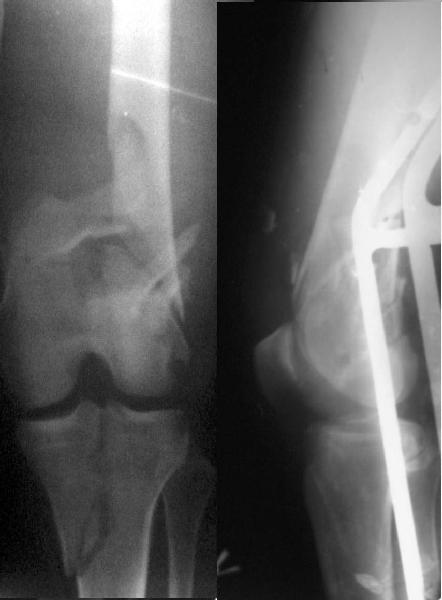

This is what we have done... As generally true for LISS look at the bone not the hardware.

Look what we would have done.

I would not say that the LISS is superior to the nail. If I would, I had not post original mail. I wanted to generate discussion. Your option is a very viable one. I feel a little bit shaky the distal femur, but it is just gut feeling no science behind it. Any way nice fixation, congarts!